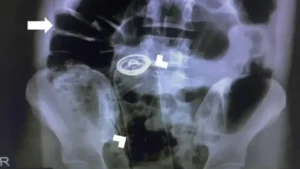

O paciente chegou à unidade de saúde reclamando de fortes dores abdominais. Durante a triagem, ele relatou aos profissionais que havia introduzido o frasco e não conseguiu removê-lo.

A equipe médica realizou os procedimentos de praxe e, diante da gravidade da situação, o homem foi encaminhado para o centro cirúrgico, onde passou por um procedimento para a retirada do objeto.